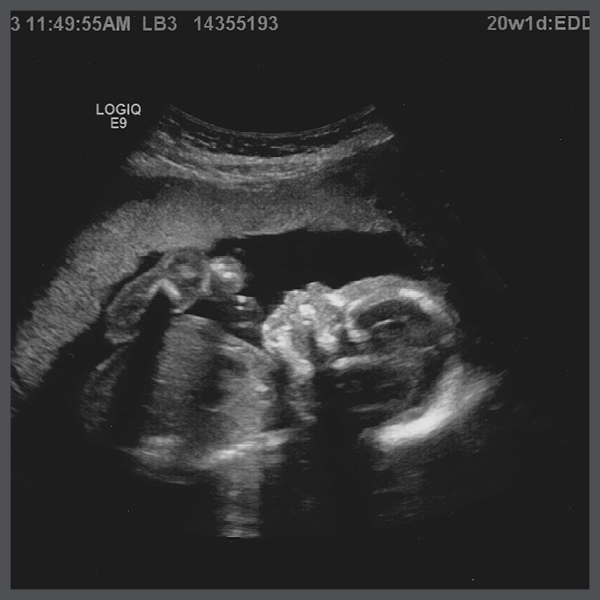

The Ultrasound/We’re Pregnant! Post – Ah, babies. They are popping up everywhere on the news feed. It seems like almost a monthly occurrence. Not that I am – by any means – ready to procreate, but seeing my friends actually having babies on purpose does lead to a similar life analysis as the engagement posts. Why am I not there yet? I am still trying to effectively support myself, how could I do that for another human? All of these social announcements are – of course – followed by an obscene amount of baby pictures. Which are frustratingly cute.